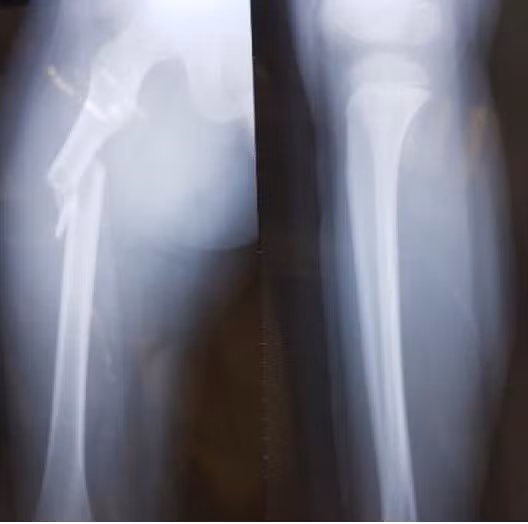

| Hình ảnh khi xương đùi của học sinh Trần Chí Kiên được chụp X-quang. Ảnh: NVCC. |

Cùng ngày, cháu được đưa đi cấp cứu tại Bệnh viện Nhi Trung ương. Theo bác sĩ, Kiên bị gãy xương đùi phải nhưng bó bột không thành công vì vết thương quá nặng. Nam sinh được chuyển sang Bệnh viện Việt Đức, Hà Nội. Bác sĩ chỉ định em phải mổ, nẹp vít xương.

Theo bác sĩ, nếu Kiên chỉ chạy chơi trong sân trường, em khó bị gãy xương đùi. Đây là bộ phận cứng, người không có bệnh lý về xương phải bị lực tác động mạnh mới có thể gây tổn thương. Đồng thời, Kiên có vết xước sau hông trái, dự đoán sau khi bị đâm mạnh, cháu ngã ngửa về phía sau.